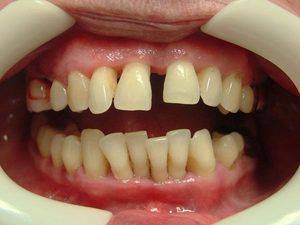

Десневой край заметно снижается, шейка корня оголяется практически наполовину. Средняя стадия сопровождается неприятным запахом изо рта, деформацией зубного ряда.

Оголение передней группы зубов